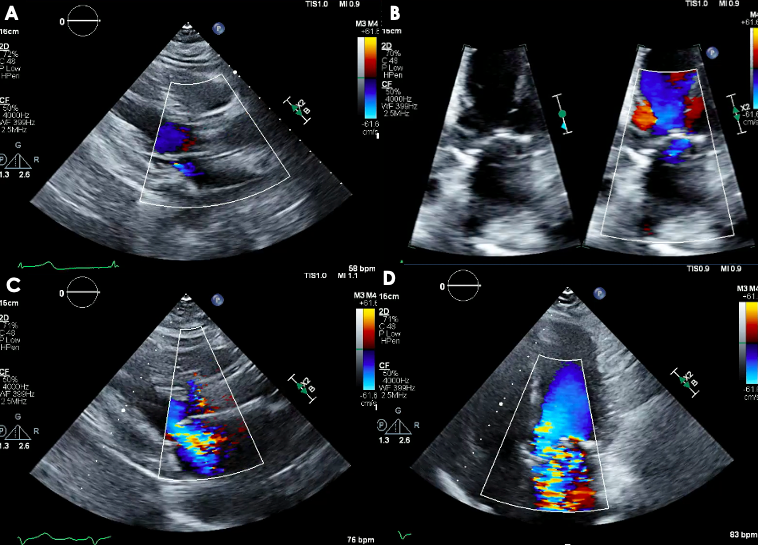

The patient underwent transfemoral TAVR with a 25-mm Navitor valve (Abbott) after initial ballon aortic valvuloplasty (BAV). TTE and angiography documented normal valve positioning and function, and normal coronary perfusion. Within a few minutes of the deployment of the valve, the patient developed persistent hypotension and vasopressors were initiated. TTE showed anteroseptal hypokinesis and severe MR with a centrally directed jet (Figure 1C and D; Video 5). The patient was intubated, and transesophageal echocardiogram (TEE) confirmed severe MR with a broad, centrally directed jet from poor mitral leaflet coaptation (Figure 2A and B; Videos 6 and 7). A diagnostic left heart cardiac catheterization showed no changes in the underlying CAD. An intra-aortic balloon pump was placed, and TEE showed MR improvement from severe to mild (Figure 2C; Video 8). The patient was moved to the cardiac intensive care unit for continuous hemodynamic monitoring. Her clinical course progressively improved and she was discharged home on post-procedure day 7 in stable condition.

Severe functional MR with ensuing cardiogenic shock is a rare complication after TAVR. In this case, it was likely due to transient left ventricular dysfunction because of hypoperfusion from rapid pacing during BAV and TAVR deployment. Intra-procedural echocardiography is crucial for rapid detection and differential diagnosis of cardiogenic shock after the TAVR procedure and can be lifesaving, as demonstrated by our case.